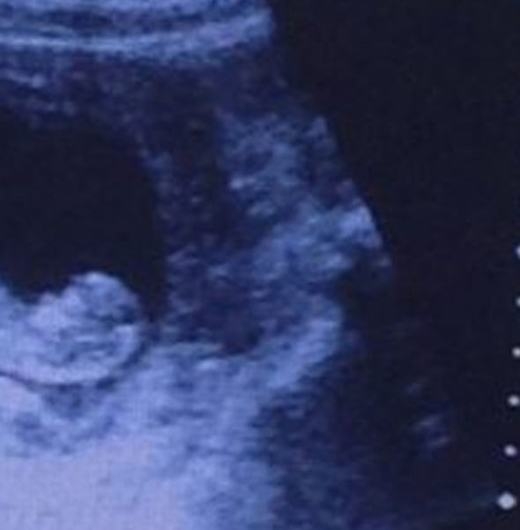

Mới đây, hình ảnh siêu âm thai của một người phụ nữ đã khiến cộng đồng mạng hoang mang tột độ. Cụ thể là trên bức ảnh đó bất ngờ xuất hiện hình ảnh giống như của “quỷ dữ” bên cạnh bào thai. Từ lúc bức ảnh được đăng tải trên mạng đã có rất nhiều luồng ý kiến trái chiều về hình ảnh của “quỷ” đó.

Thông thường, khi siêu âm người ta chỉ nhìn thấy em bé. Tuy nhiên mới đây, hình ảnh “quỷ dữ” xuất hiện trên màn hình bên cạnh thai nhi làm cho mọi người không khỏi giật mình. Nếu nhìn lướt qua, có thể nhiều người nghĩ đây là một bức ảnh siêu âm bình thường như bao ảnh siêu âm khác.

Theo tờ báo nổi tiếng của Anh Express mô tả, hình ảnh siêu âm có thể bình thường khi mới nhìn vào với thai nhi trong bào thai. Nhưng nếu quan sát kĩ hơn, nhất là ở góc phải, ta sẽ thấy hình ảnh của một người khác với khuôn mặt dữ tợn đang nhìn vào thai nhi.

Cái này mới là quỷ đỏ hình gốc nè ,tin từ báo mang tiếng quân hại nhân dân chụp tại xưởng đẻ Từ Dũ :